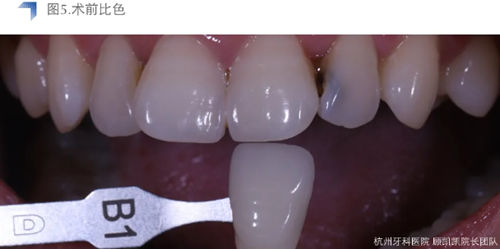

待貼面制作修整完成后,用DMG Vitique Tr.色配套試色糊劑口內(nèi)試色。

小結(jié):Vitique Tr.在本病例中試色與術(shù)后粘接未見明顯差異,能恰當(dāng)表現(xiàn)e.max B1 mt的通透度和明度,美學(xué)效果優(yōu)異。考慮到患牙較近髓,長期隨訪和術(shù)后常規(guī)勿咬硬物及冷熱刺激,十分必要。